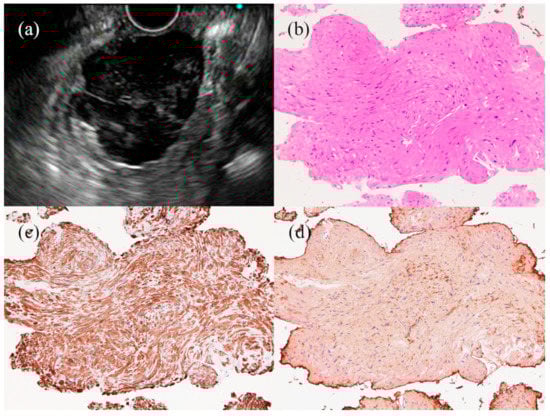

- Fujita, A.; Ryozawa, S.; Kobayashi, M.; Araki, R.; Nagata, K.; Minami, K.; Tanisaka, Y.; Kobatake, T.; Mizuide, M. Diagnostic ability of a 22G Franseen needle in endoscopic ultrasound-guided fine needle aspiration of subepithelial lesions. Mol. Clin. Oncol. 2018, 9, 527–531. [Google Scholar] [CrossRef]